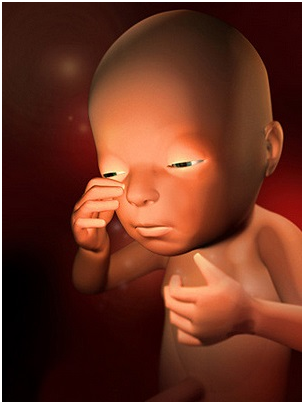

怀孕第30周你一直在给宝宝讲故事、唱歌吗?如果是的,那么现在的宝宝已经非常熟悉你的声音了!这...

怀孕第30周你一直在给宝宝讲故事、唱歌吗?如果是的,那么现在的宝宝已经非常熟悉你的声音了!这... -

怀孕第31周这周宝宝的眼睛时开时闭,他大概能够看到子宫里的景象了!你可能时常会感到呼吸越发困...

怀孕第31周这周宝宝的眼睛时开时闭,他大概能够看到子宫里的景象了!你可能时常会感到呼吸越发困... -

怀孕第32周这个时候,你一定要坚持每两周一次的体检,检查时要注意脐带的扭转情况。最近你可能会...

怀孕第32周这个时候,你一定要坚持每两周一次的体检,检查时要注意脐带的扭转情况。最近你可能会... -